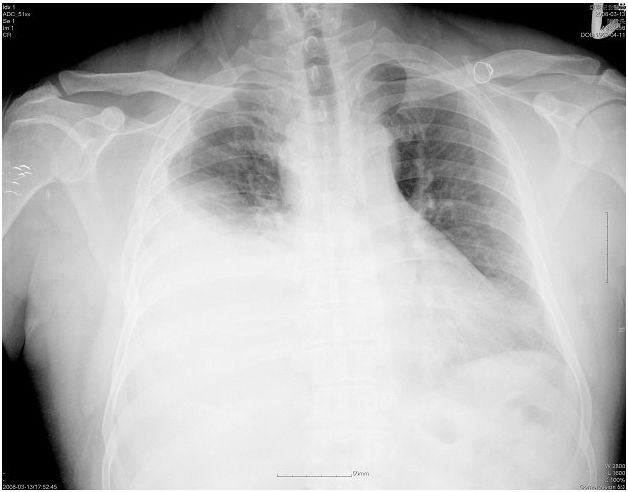

3. 68歲男性主訴多年來咳嗽多痰,胸部電腦斷層掃描如圖所示,下列有關此病人診療之敘述,何者正確? (A) 理學檢查若有喘鳴聲(wheezes),即表示有合併支氣管性氣喘病 (asthma) (B) 痰抹片檢查常顯示很多嗜中性白血球(neutrophils) (C) 此病人之正面胸部X光應呈現正常 (D) 肺功能檢查之主要變化是肺活量(VC)降低 (E) 如果連續三天都出現血痰,就是手術肺葉切除之時機